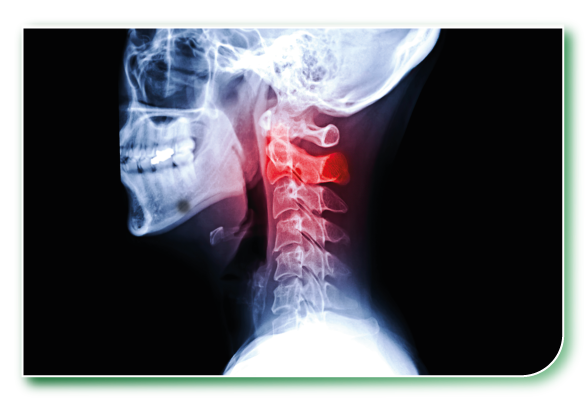

頸椎係由 7 節脊椎骨組成,負責支撐頭部重量、維持活動角度。

當長時間維持低頭姿勢或姿勢不良,就會令頸部肌肉過度繃緊,頸椎間盤受壓,引起發炎、神經壓迫,甚至退化變形,導致頸椎痛。

長期低頭會令頸椎處於非自然前傾狀態,承受超過正常5–6倍重量壓力,頸椎慢慢出現退化、移位或骨質增生。

頸椎曲度異常(直頸/反弓)

• 本來應該係C形嘅自然頸椎曲線,變直甚至反向